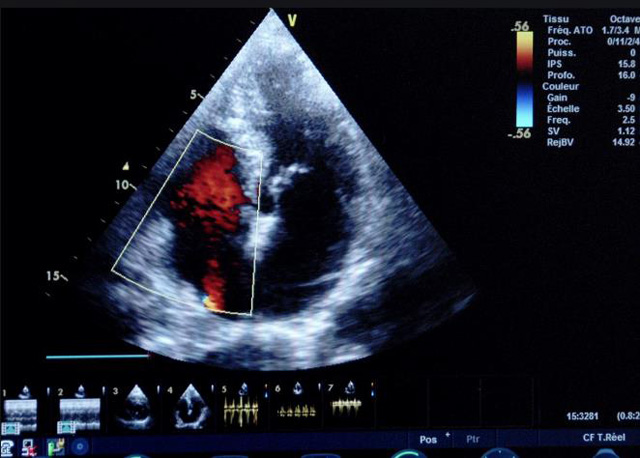

二、彩色室壁運(yùn)動分析

(一)基本原理彩色室璧運(yùn)動分析,從整體散射數(shù)據(jù)中識別心內(nèi)膜邊界,并與前一幀彩色不同,心臟收縮或舒張期開始到結(jié)束時心內(nèi)膜的全部過程。每一次順序顯示結(jié)束后,原來的彩色自動消失,以便進(jìn)入下一個顯示過程。其結(jié)果是獲得對應(yīng)于每一個心動周期的彩色顯示,描繪特定周期內(nèi)室壁運(yùn)動的時間運(yùn)動軌跡。

(二)操作步驟根據(jù)背向散射數(shù)據(jù)中將心內(nèi)膜運(yùn)動的位移過程分類為組織或血液的原理,邊緣檢測跟蹤心內(nèi)膜和血液的界面。橙色表示收縮期的開始,收縮期不同時相逐幀顯示色彩均疊加在收縮末期最后一幀圖像中。檢查時,可按以下步驟進(jìn)行:

①顯示較為理想的二維圖像,常用切面有心尖四腔心、二腔心、左心室長軸和左心室乳頭肌水平短軸切面。

③啟動CK系統(tǒng),啟動后劃定感興趣區(qū)域。同時記錄的心動圖R波頂點(diǎn)為舒張末期,T波終點(diǎn)為收縮末期,顯示RT間期的CK彩階圖,連續(xù)記錄3~ 5個心動周期。

(三)檢測節(jié)段性室壁運(yùn)動異常,研究冠心病患者左心室功能和分析局部室壁運(yùn)動過程中。測量每一節(jié)段室壁的運(yùn)動量,運(yùn)動正常的節(jié)段彩帶色彩均勻?qū)哟喂庹_\(yùn)動減弱的節(jié)段,厚度薄層次不全。心內(nèi)膜位移幅度和速度均減低。心內(nèi)膜位移幅度和速度甚低或難以測得。正常的多層彩帶消失,呈現(xiàn)紅色色帶,心內(nèi)膜位移呈負(fù)向,幅度和速度亦減低。急性心肌梗死的患者中可用于識別存活心肌抑或壞死心肌。多巴酚丁胺負(fù)荷試驗存活心肌的心內(nèi)膜位移幅度增高,停藥后即消失,而壞死心肌則無上述表現(xiàn)。實時檢查冠心病的節(jié)段性室壁運(yùn)動異常,有時候通過發(fā)現(xiàn)局部心肌運(yùn)動的時相異常,對于心臟傳導(dǎo)障礙的診斷也可能有幫助。